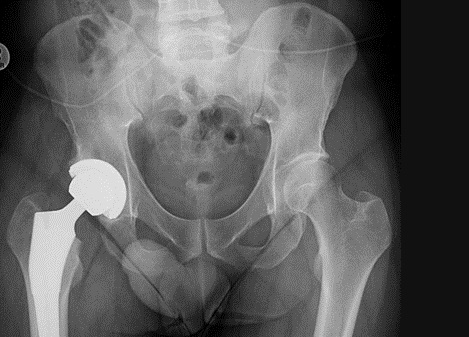

Fig4. - Avascular necrosis right hip.

Fig4. - Treated with cementless total hip replacement.